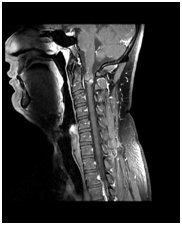

Súlyos trauma a nyaki gerinc: a törés-zavar a C5 csigolya test, súlyos tömörítés az agytörzs, jeleivel gerincvelő-ödéma, a teljes gerinccsatorna szűkület szintjén a törés. MR kép prevertebrális vérömleny.

T1VI T2VI (keverjük) T2VI